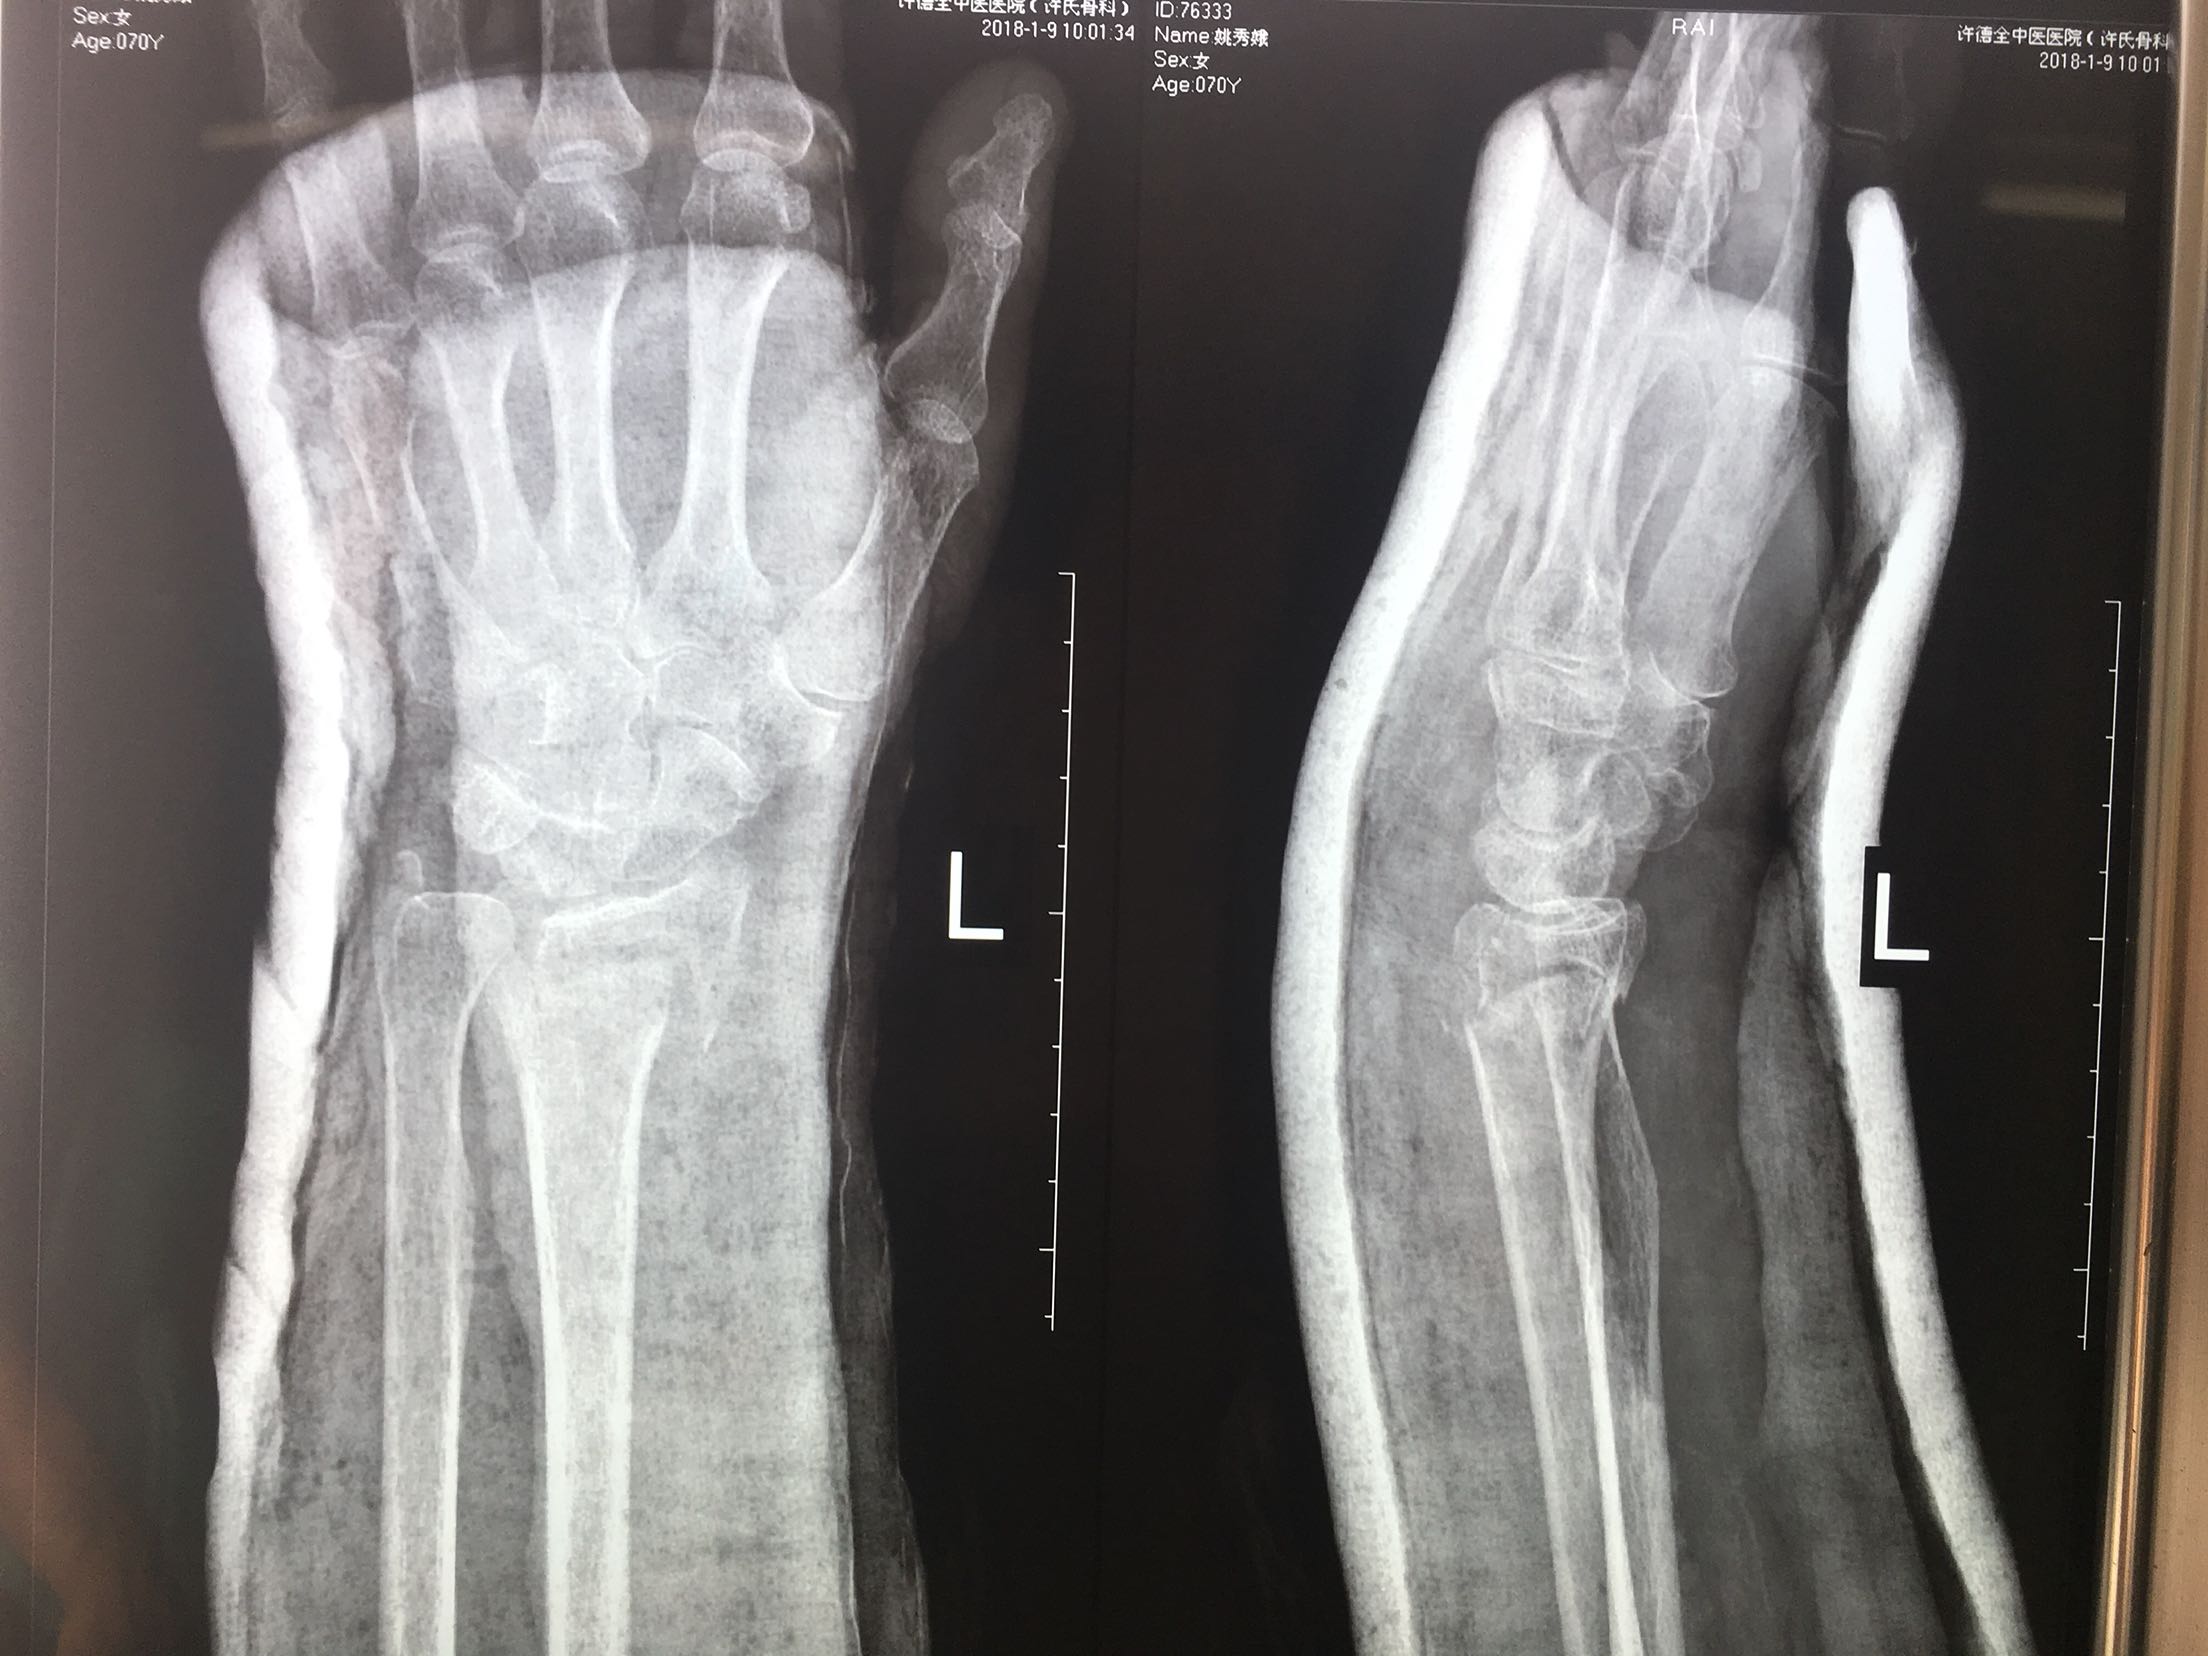

一例保守治疗失败的colles骨折

患者,女性,70岁,摔伤后左腕关节肿痛畸形3天。

左腕部肿胀,局部压痛,皮色皮温正常,畸形,远端感觉血运良好。

在臂丛麻醉下行切复内固定术,术后抗炎,消肿对症处理。